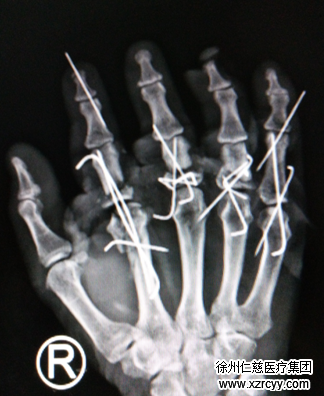

晚上8点钟,手术开始。李刚医生手术团队先是对患者受损的右手彻底清创,手法复位各指骨折断端及脱位关节,并用克氏针将骨折部位一一固定。1根、2根、3根……整整15根克氏针,把患者手部所有骨折部位均予以固定。随后,医生将断裂肌腱一一缝合,然后在显微镜下探查患者损伤的血管神经,将受损的血管神经一一缝合,最后又修复手掌手背的撕脱皮肤……当最后一针缝合完毕,已是凌晨1点钟。